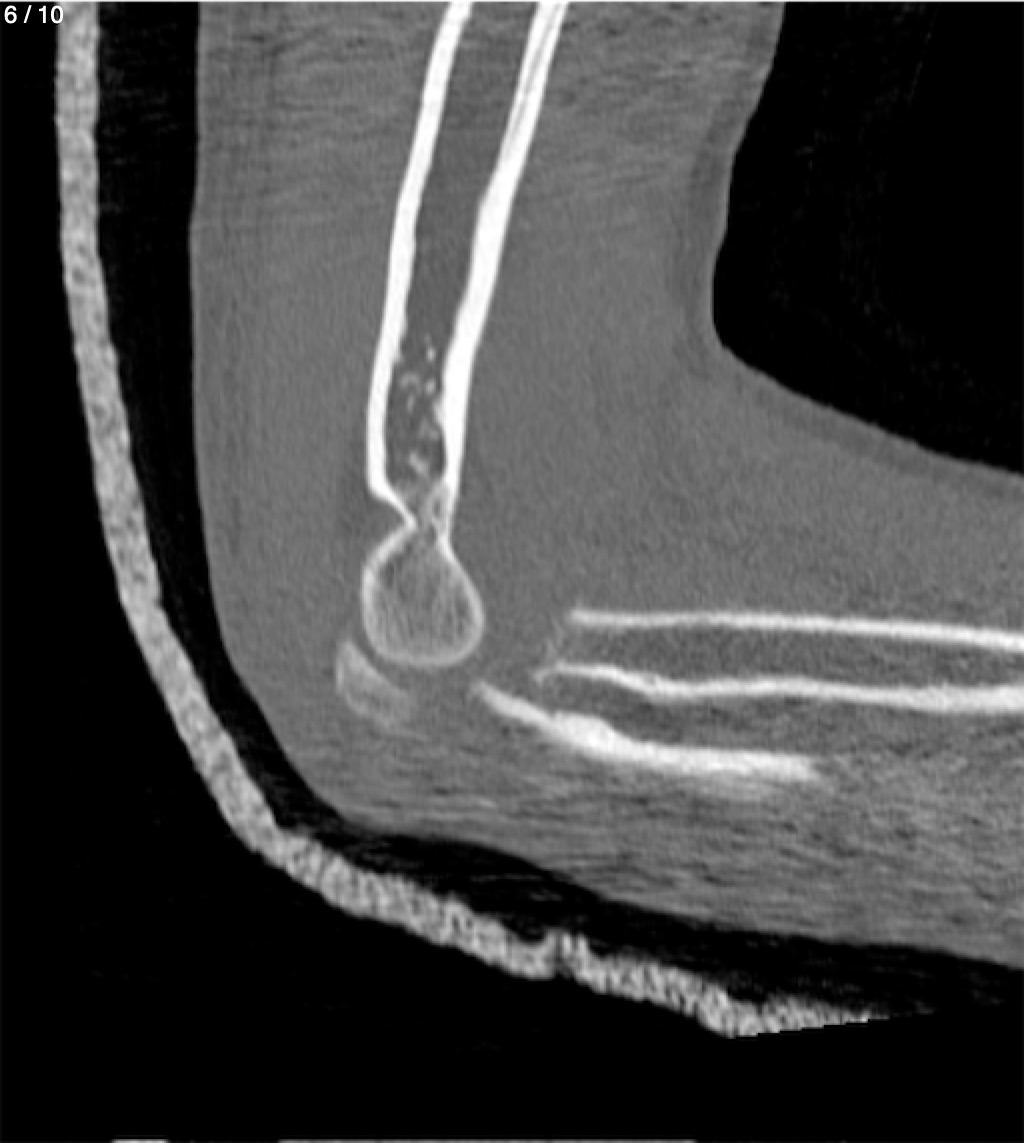

Antonio Dominguez Tino 21 A - Tac Codo Izq